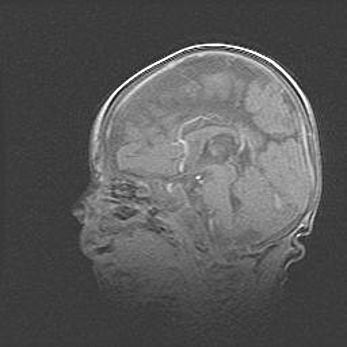

Сообщающаяся гидроцефалия. Кистозная энцефаломаляция головного мозга.

Возраст: 3 месяца 4 дня

Вес: 3100 г

Пол: женский

Окружность головы: 34 см

Срок гестации: 31 неделя

Кистозная энцефаломаляция головного мозга - одна из форм поражения головного мозга в детском возрасте. Характеризуется возникновением множественных и распространённых кист в коре, белом веществе и подкорковых образованиях головного мозга у плодов, новорождённых и детей раннего возраста. Развитие кистозной энцефаломаляции связано с внутриутробной асфиксией и гипотонией, родовой травмой, тромбозом синусов, пороками развития сосудов, инфекциями, сепсисом и другими причинами. Наиболее значимые инфекционные агенты: вирусы простого герпеса, цитомегалии, краснухи, токсоплазмы, энтеробактерии, золотистый стафилококк и другие.